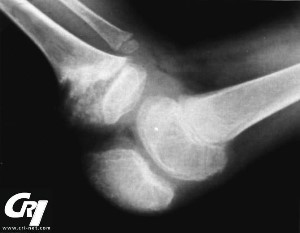

Articular (joint) affects are present in variable degrees in most patients with NOMID/ CINCA. Periodic swelling without damage between flare-ups of inflammation are generally present. There can also be disfiguring and uncontrolled anomalous changes to the growth cartilage, often at the knees, suggestive of a pseudo-tumor growth. Many people that have developed this have enormously enlarged kneecaps (patellas) and other bony overgrowth at the large joints. This can occur in approximately 50% of people with NOMID. Often, biopsy findings show disorganized cartilage with no inflammatory cells present.

In the past, physicians thought that the enlarged, bony overgrowth was a necessary characteristic in order to diagnose someone with NOMID/CINCA, but now it is known that not all people with this syndrome develop the irreversible, disfiguring and debilitating damage to the joints. There is a great degree of variance in inflammation, deformity and pain in the joints with NOMID/CINCA.